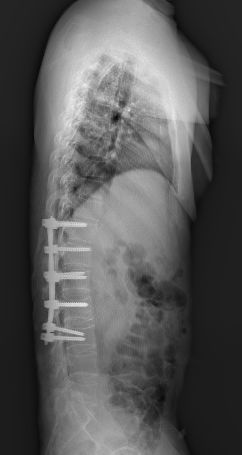

深圳市中医院骨三科的何升华主任经过仔细的检查、看片以后得出诊断结论:病人为强直性脊柱炎合并L1、L2椎体爆裂骨折。

全脊柱正侧位显示骶髂关节间隙消失

脊柱竹节样融合改变

腰椎MRI及CT显示腰1 腰2椎体新鲜压缩骨折

术后复查见腰1、腰2椎体高度恢复,螺钉位置满意